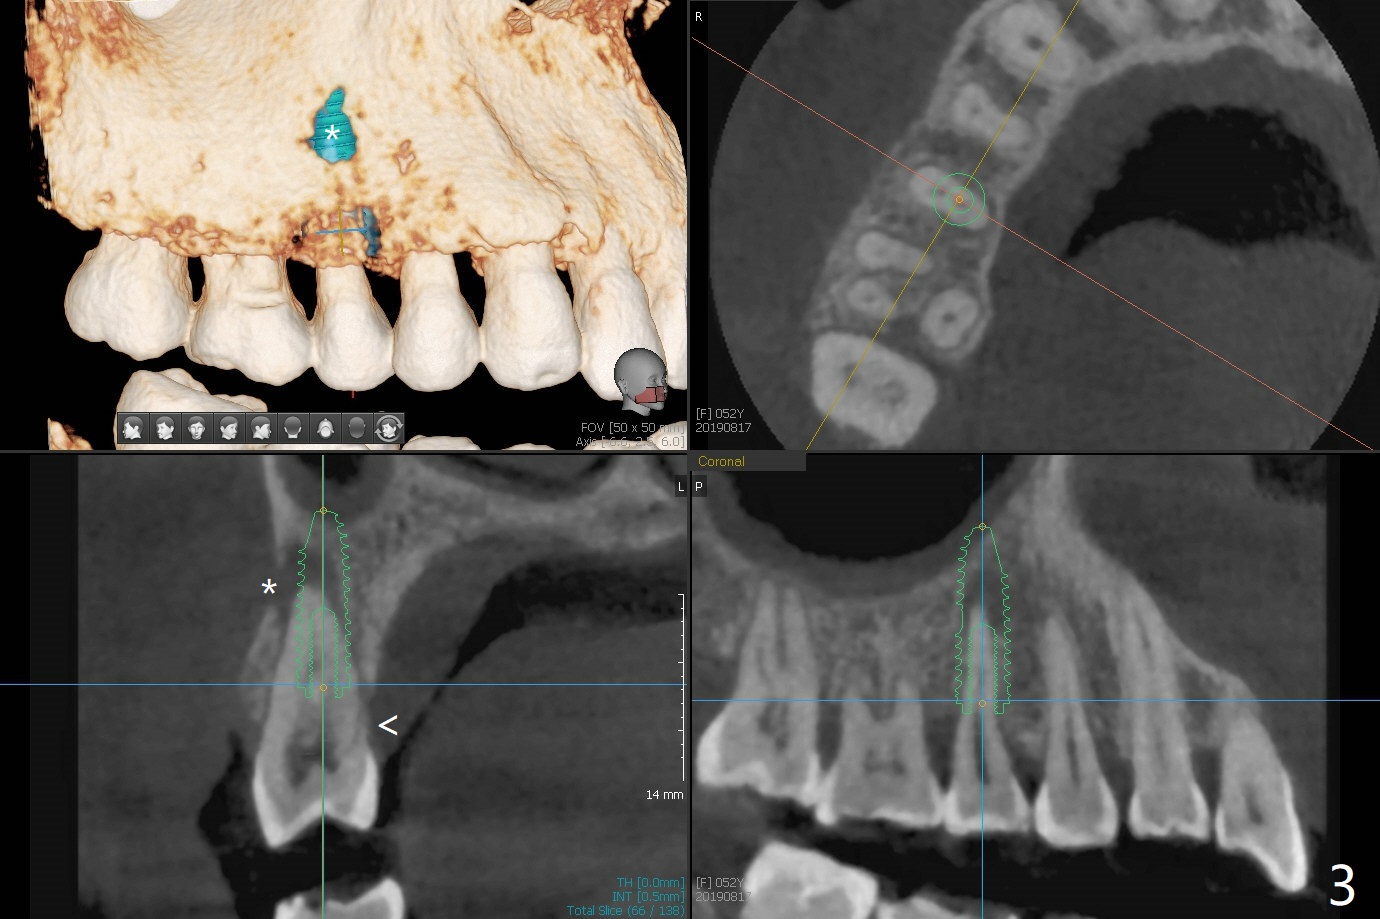

A 52-year-old woman had palatal periodontal infection at #2 a half month earlier (Fig.1,2), which was treated with Arestin. When she returns, the tooth #4 has palatal subgingival oblique fracture (Fig.3 <), interfering with mastication. Due to emergency, free hand immediate implant is planned. The buccal apical defect (Fig.3 *) will be repaired with PRF membrane (x1) and allograft after osteotomy (with gauze in place). A 4.5x20 mm tissue-level implant will be placed (Fig.4) instead of a bone-level one (Fig.5).